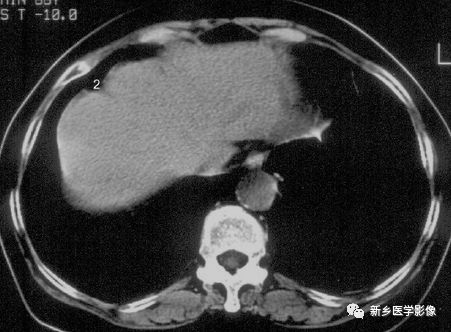

左叶肥大最常见,尾叶肥大次之。表现为体积增大,肥大的肝左叶最大前后径大于右叶,或异常延长。尾叶肥大:尾叶呈分叶状或球形增大。尾叶肥大与外生性肝癌鉴别:前者密度均匀,边缘光滑,血管走行自然,平扫及增强密度同肝实质。